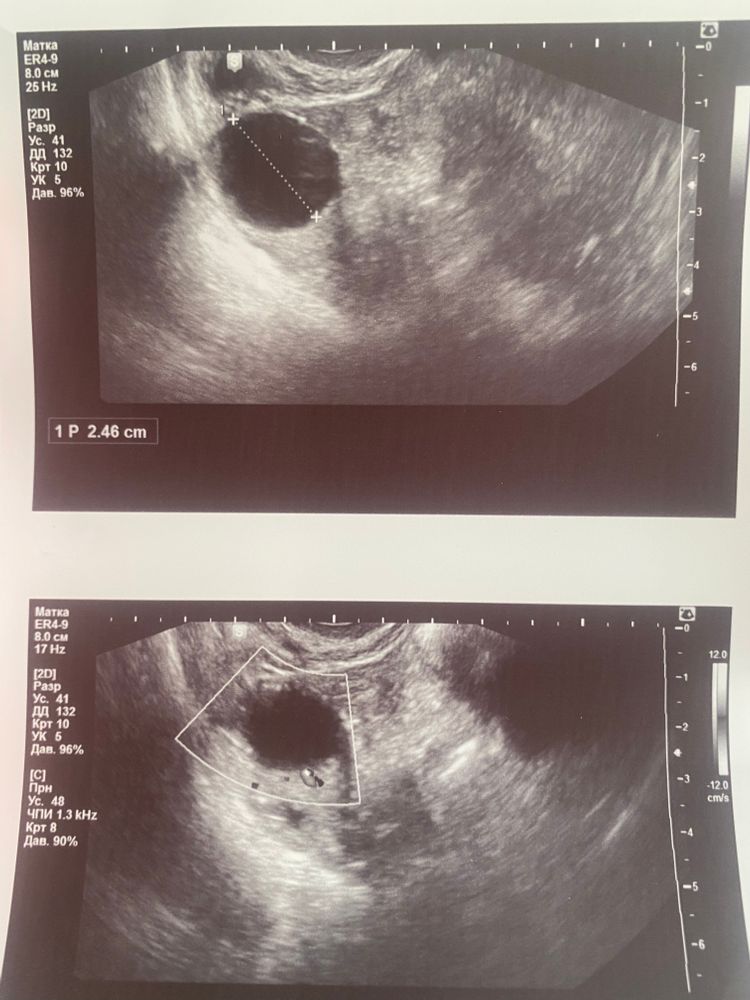

16 дц ДФ уже 23мм (считай за сутки после приема ре)

17дц вот тут я делала узи в другом месте, эндометрий переходного типа в секреторный, жидкость за маткой есть до 6 мм, и вот тут самое интересное, врач узи не может дифференцировать это ДФ, ЖТ типа овуляция вот только только случилась пару часов назад, либо это киста🤦🏼♀️ По моему субъективному мнению, по структуре очень похоже на фоликул, размер его 25 мм, кровоток единичный. Он либо прям лопнет вот вот, либо это уже реальная киста. Замечу, кист у меня не бывает фолликулярных. Цикл Крио чистый, без укола хгч, пишу ре, говорит начинаем утрик в ночь, на осмотр по решению переноса 11.04 - вторник, на третий день приема прогестерона получается.

фото прикрепляю, девочки, вопрос лишь в том, как думаете, это фолик или уже ЖТ? Или похоже на кисту?